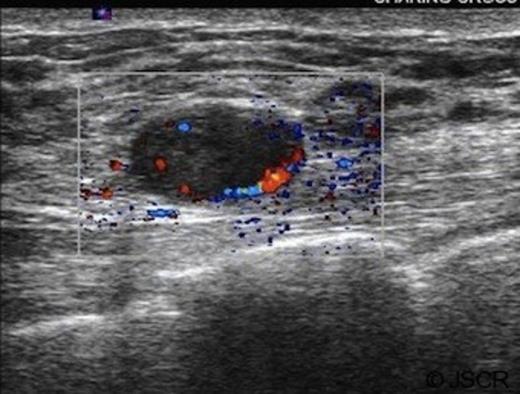

A mammogram was reported as normal (M2) (Figure 2). An ultrasound scan performed showed a lesion at the 2,2 site, with appearances suggestive of a fibroadenoma (U2) (Figure 3). Core biopsy showed fibrocystic change.